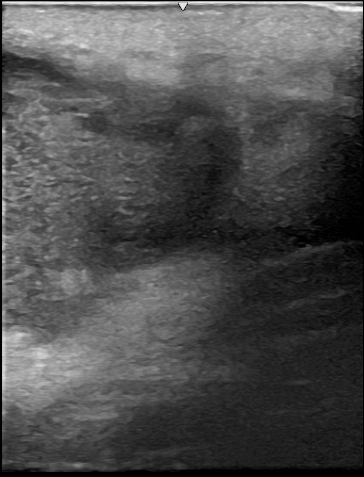

診察時、後頚部に直径80mmの発赤を伴うしこりがあり、超音波検査により典型的な感染性粉瘤と診断されました。一部、僧帽筋筋膜にも炎症が波及していました。採血で糖尿病も認められたため、糖尿病の治療と並行して粉瘤の治療を行う方針となりました。

初回手術術中